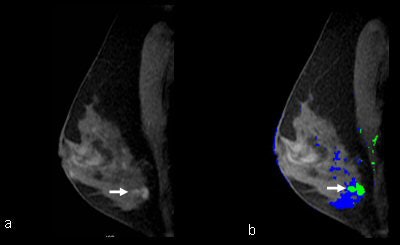

| MR images, with and without CAD, applied in a 49-year-old BRCA1 patient with a left breast MRI-detected invasive ductal carcinoma, diagnosed at MRI-guided wire localization and surgical excisional biopsy. (a) Sagittal T1-weighted 2D SPGR fat-suppressed (150/4.2; flip angle, 50°; matrix, 256 x 128; field-of-view 18 cm; slice thickness, 3 mm) image shows a heterogeneous enhancing lobulated mass (arrow) in the central lower left breast. (b) CAD assessment of the lesion demonstrated enhancement at the all the threshold levels. At 80% threshold CAD color mapping of the delayed enhancement pattern shows predominantly green with a dot of red that differs from the mainly blue background. This was therefore assessed as malignant based on CAD. |